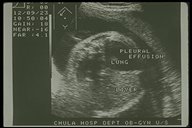

Prenatal ultrasonography showed bilateral congenital chylothorax, massive pleural effusion was detected in both chest cavity